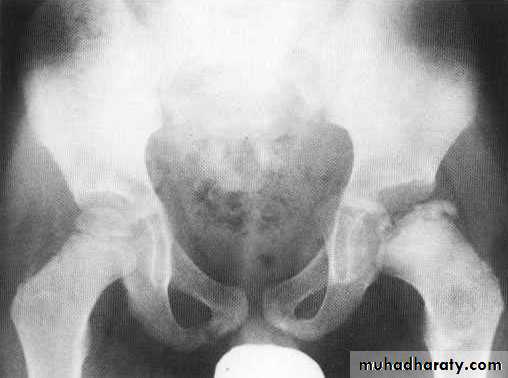

NEUROPATHIC ARTHRITIS (CHARCOT'S JOINT)

• Primary loss of sensation in a joint leads to arthropathy. Distribution helps determine etiology.• Causes

• Diabetes neuropathy: usually foot

• Tertiary syphilis : usually knee

• Syringomyelia: usually shoulder

• Radiographic features

• Common to all types

• *Joint instability: subluxation or dislocation

• *Prominent joint effusion

• --- Hypertrophic type, 20%

• Marked fragmentation of articular bone

• Much reactive bone

• --- Atrophic type, 40°/0

• Bone resorption of articular portion

• --- Combined type, 40%